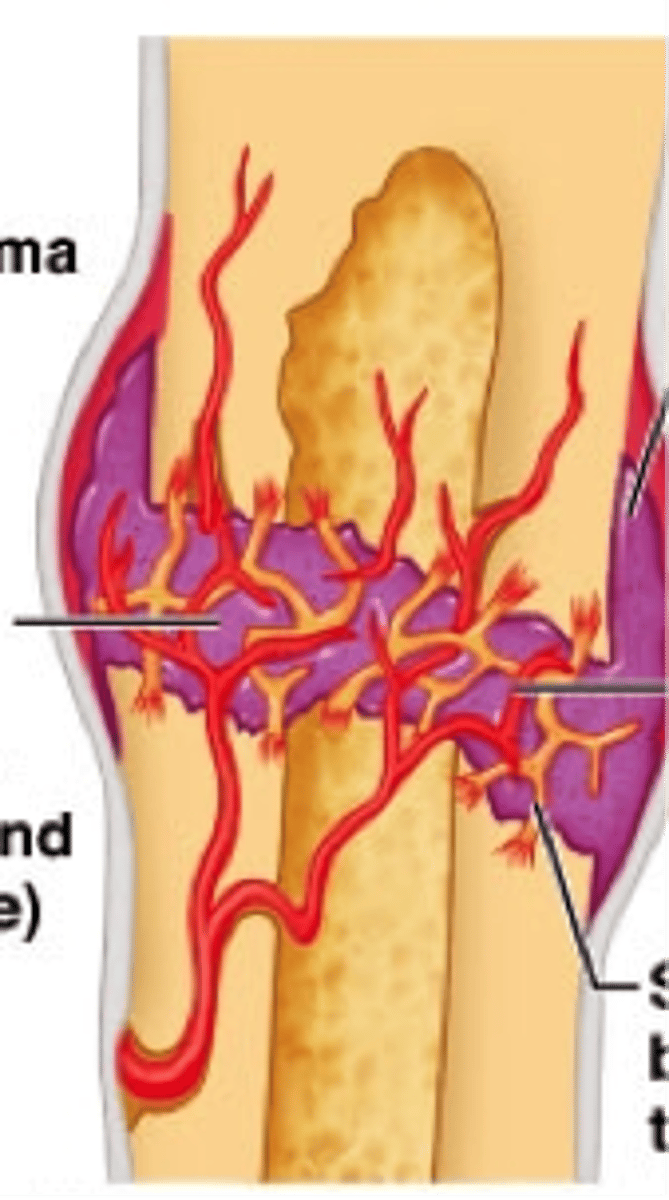

hematoma

1st step in healing a broken bone: an elevated, localized collection of blood trapped under the skin that usually results from trauma

fibrocartilage callus

2nd step in healing a broken bone:

connective tissue forms scaffolding to close the gap

bony callus

3rd step in healing a broken bone: osteoblasts fill spongy bone with osteoid to create compact bone patch

bone remodeling

4th (last) step in healing a broken bone: osteoclasts & osteoblasts reshape the bony callus formation